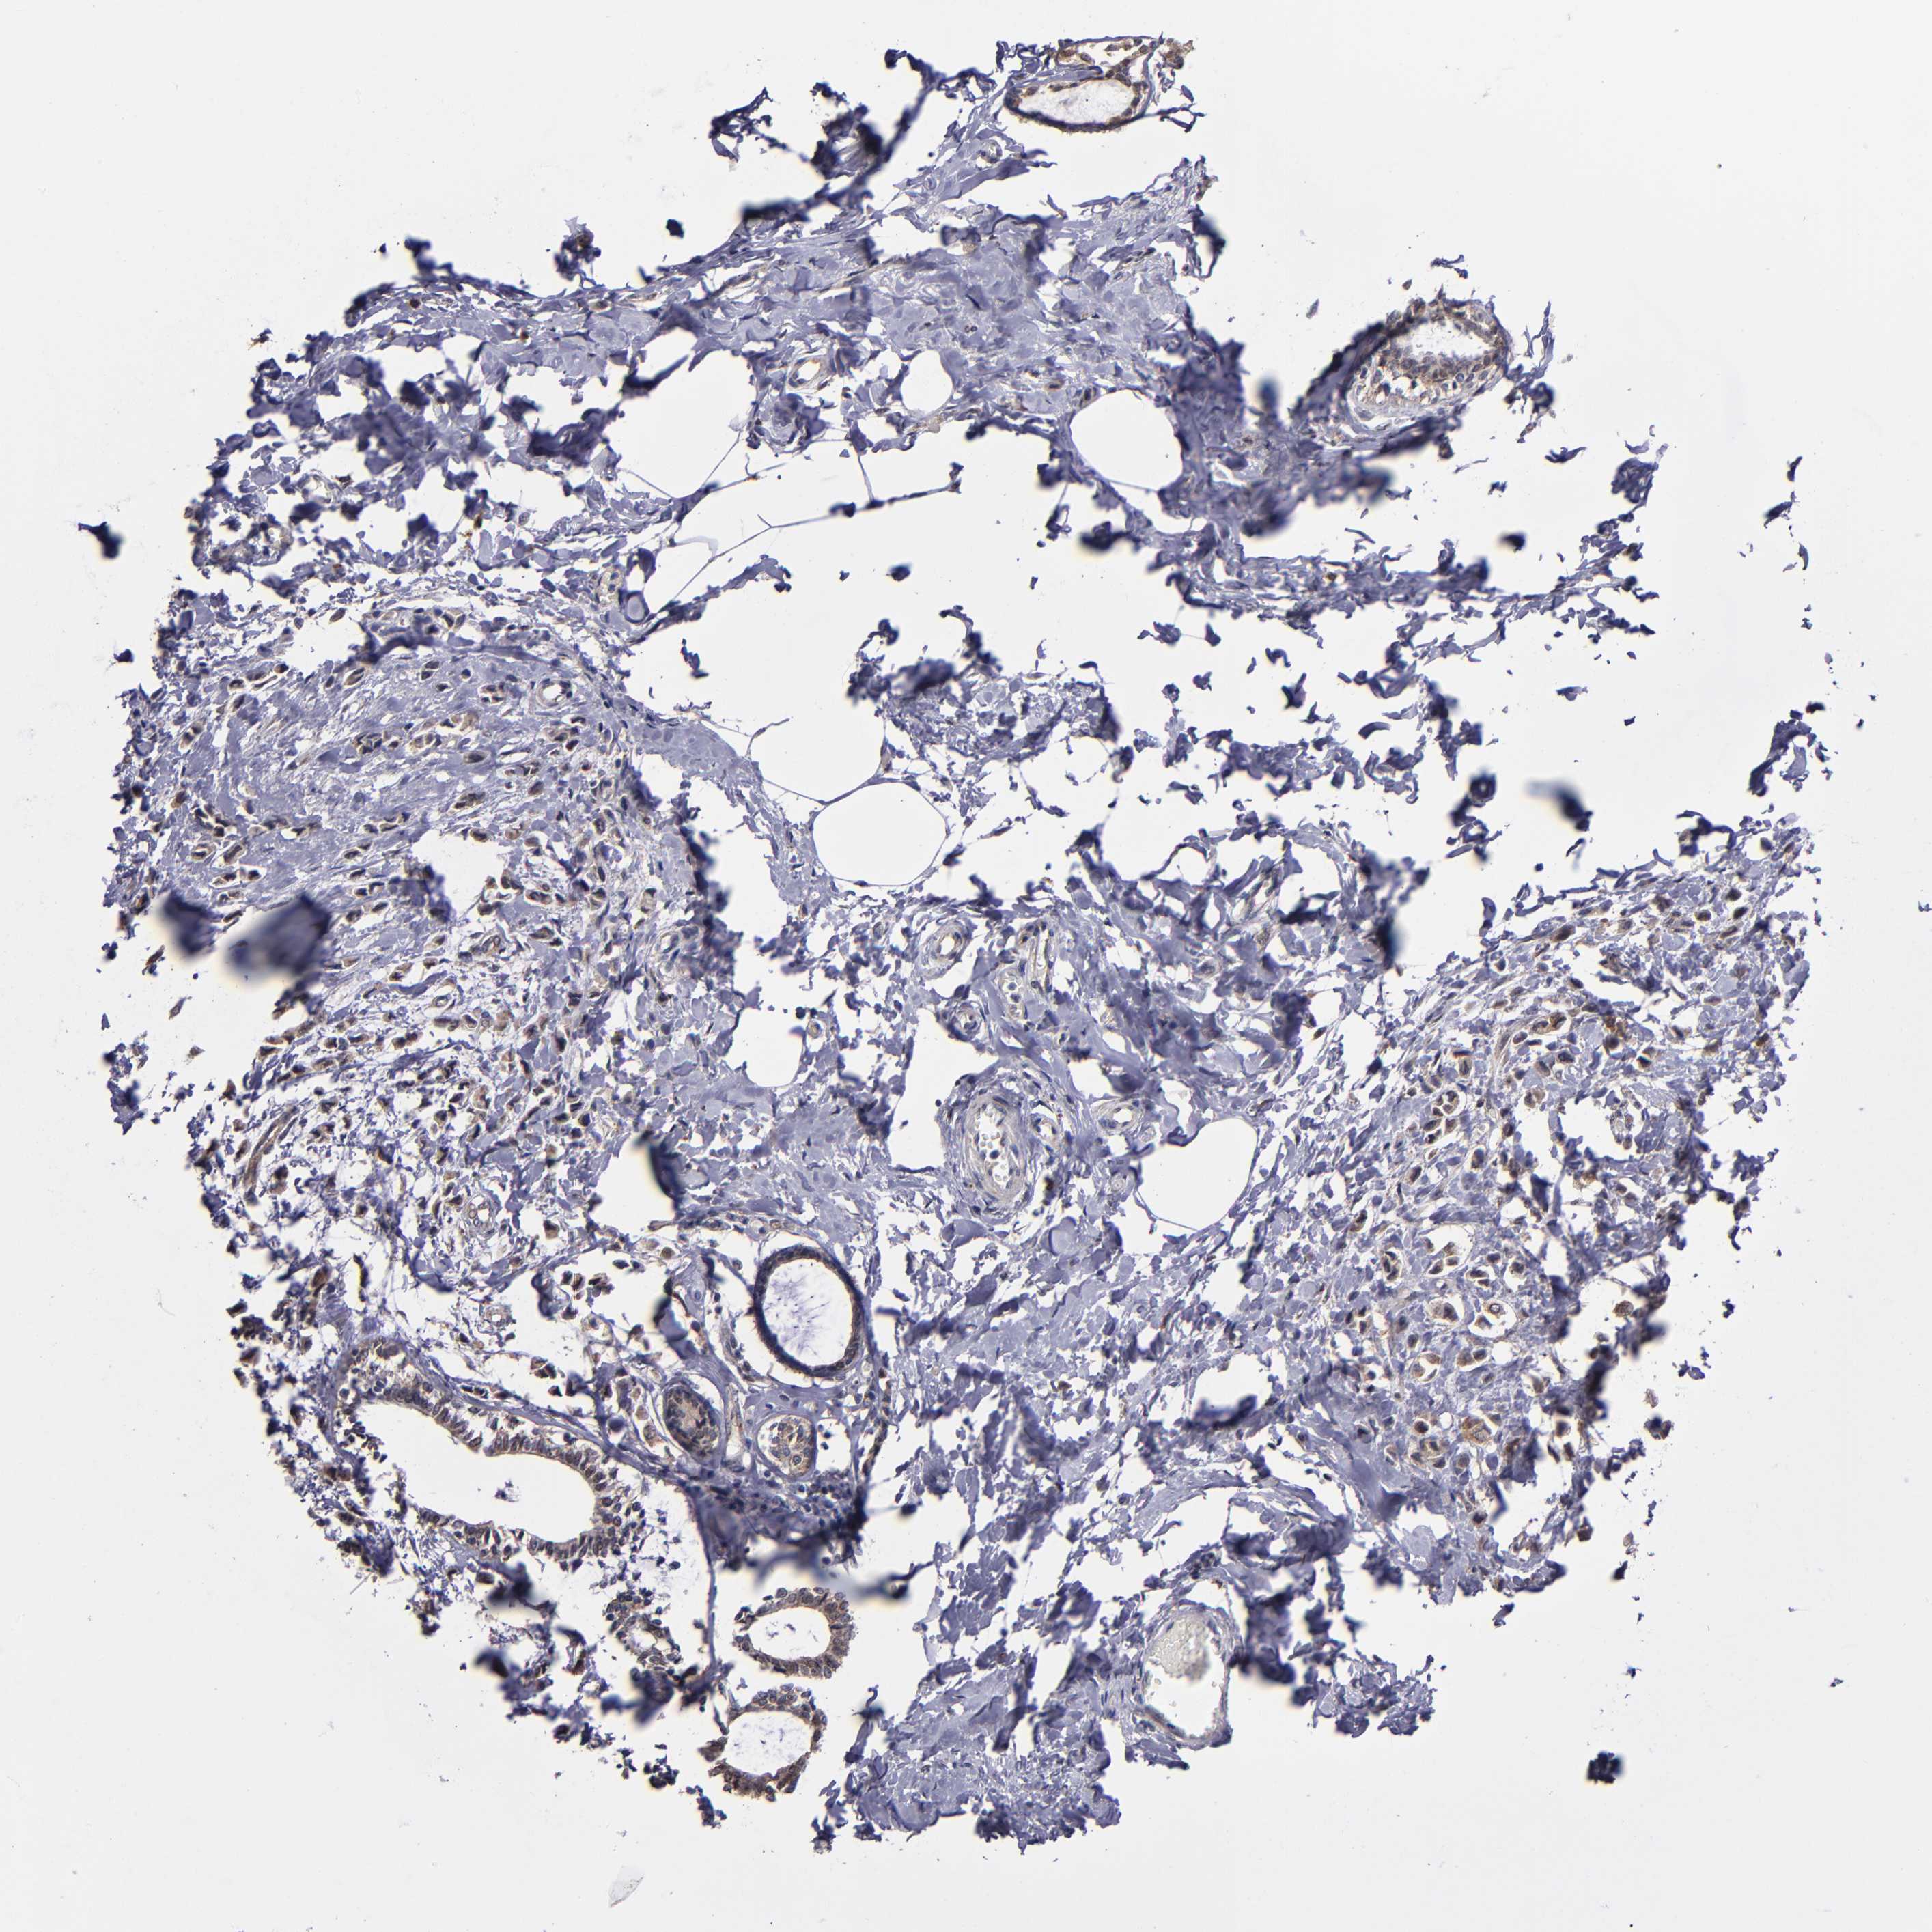

BRCA TCGA BRCA VALIDATION PROTEIN EXPRESSION

ANTIBODIES

AND

VALIDATION